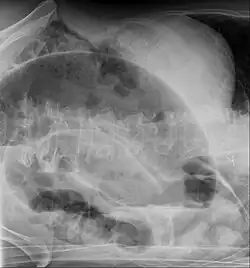

CT scan of a small bowel volvulus. It shows two juxtaposed segments of narrowing, which is the spot of mesentery rotation. The other signs indicate strangulation.

An x-ray of a person with a small bowel volvulus.